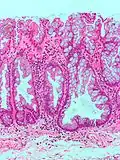

Peutz-Jeghers Polyp All digestive tract Smooth muscle bundles between nonneoplastic epithelium, "Christmas tree" appearance No

Peutz–Jeghers syndrome

Micrograph of a Peutz–Jeghers colonic polyp – a type of hamartomatous polyp. H&E stain.